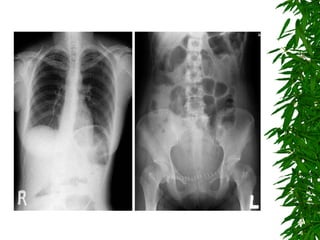

Day 5 & Day 6 Patient complain left flank pain.  Still hematuria. Consult Urologist Check KUB, chest X-ray. Check Sonogram, IVP and PV

Day 5 &Day 6 Patient complain left flank pain. Still hematuria. Consult Urologist Check KUB, chest X-ray. Check Sonogram, IVP and PV